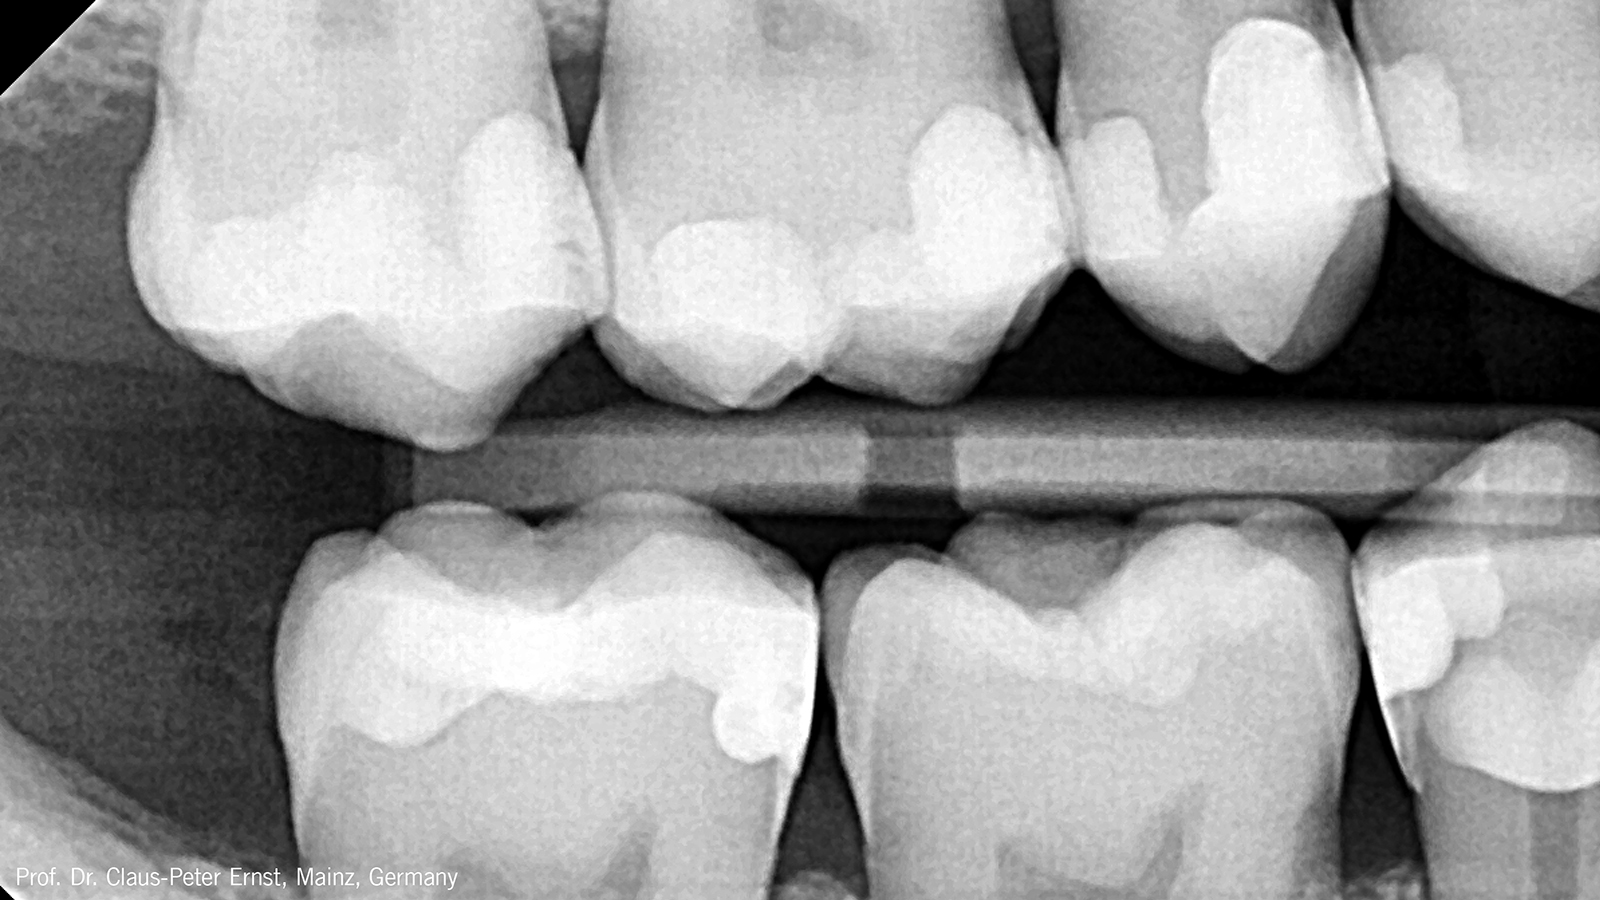

Its high radiopacity of more than 250%-AL allows for a safe and predictable diagnosis.

Is Charisma Bulk Flow ONE radiopaque?

Yes, Charisma Bulk Flow ONE fillings are easily recognized on X-rays which supports a reliable diagnosis. Its radiopacity with app. 300%-Al is much higher than the radiopacity of dentine (100%-Al) and enamel (200%-Al).